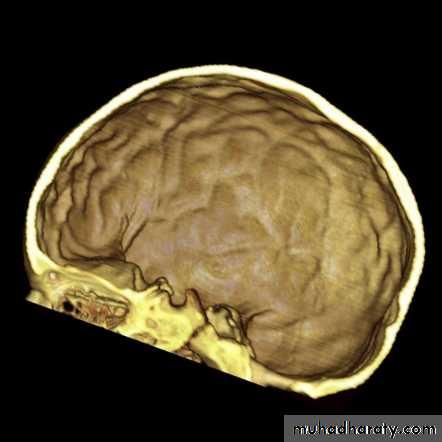

Skull X-ray findings in increased intracranial pressure

• Sutural separation in children.

• ‘Copper-beating’ marking of the cranial vault.

• Thinning of dorsum sellae.

• Erosion of the posterior clinoid process.

Copper-beating’ marking